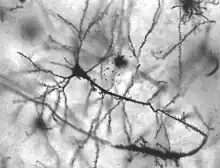

| Neurons in person with epilepsy, 40x magnified | |